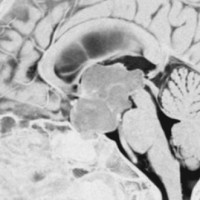

幼児の視路の毛様粘液性星細胞腫です。T2強調画像(左側)で白く高信号に写るのが特徴です。ガドリニウム増強ではまだらになっていますが,均一に真っ白に高信号になることも多いです。乳幼児のものは,ドロドロに柔らかい腫瘍です。

乳幼児時期には,病理組織像が毛様粘液性星細胞腫で,MRI T2で均一な高信号になりガドリニウムで強く増強されます。腫瘍の増大速度は速く,稀には髄液播種することもありそれが腫瘍死の原因となることもあります。奏効率の高い化学療法を早く開始する必要があります。

化学療法が有効なのは,上の画像のようにガドリニウム増強で強く増強されるタイプです,またT2強調画像で強い高信号になるものほど化学療法が有効です,要するに毛様粘液性星細胞腫の要素に化学療法が有効であるということです